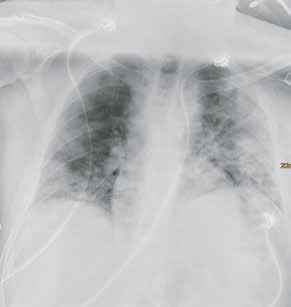

Fall 3:

Thorax-CT im Rahmen einer Lungenkrebsfrüherkennungsstudie. Die Voruntersuchung lag als externe kontrastmittelgestützte Thorax-CT vor. Bei der dosisoptimierten Low-Dose-CT liegt die Strahlenexposition nur noch im Bereich von zwei konventionellen Röntgenaufnahmen des Thorax, die Bildqualität ist für die Fragestellung nach Herdbefunden aber dennoch eindeutig ausreichend, selbst interstitielle Lungenveränderungen lassen sich hier noch beurteilen.

Prof. Dr. med. Johannes Weßling Zentrum für Radiologie, Neuroradiologie und Nuklearmedizin Abb. 3 a: kontrastmittelgestützte Thorax-CT, externe Untersuchung; DLP 216,0 mGy × cm / 3,9 mSv. Abb. 3 b: dosisoptimierte Low-Dose-Thorax-CT, Canon Aquilion Prime SP, Rekonstruktion: AiCE; DLP 13,9 mGy × cm / 0,25 mSv.